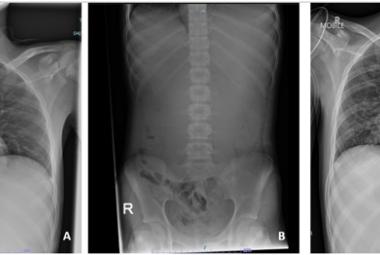

FIGURE 1: Neck re-exploration revealing intact suture at the site of primary repair